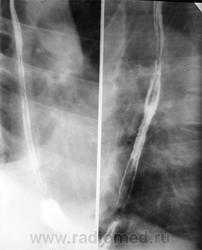

Для исследования пищевода традиционно используется рентгенологическое исследование с барием

Процесс прохождения глотков бариевой взвеси (или специального бариевого препарата) регистрируют с помощью флюороскопии в реальном масштабе времени. Частое показание к рентгенологическому исследованию пищевода - диагностика желудочно-пищеводного рефлюкса. Он проявляется обратным забросом бариевой взвеси из желудка в пищевод при исследовании в горизонтальном положении или в положении Тренделенбурга. В случае обструкции пищевода инородным телом рентгенологическое исследование позволяет немедленно установить его уровень и выраженность. С помощью этого метода хорошо видны участки расширения и сужения пищевода при доброкачественных стриктурах (рубцовых, ахалазии). Для ахалазии характерно расширение проксимальной части пищевода и сужение его дистального отдела в форме «клюва». При опухолях пищевода (доброкачественных и злокачественных) виден дефект наполнения пищевода. Характерным признаком злокачественных образований (рака) является изъязвление слизистой и изменение ее рентгенологического рисунка, ригидность стенок пищевода, неровные контуры опухоли